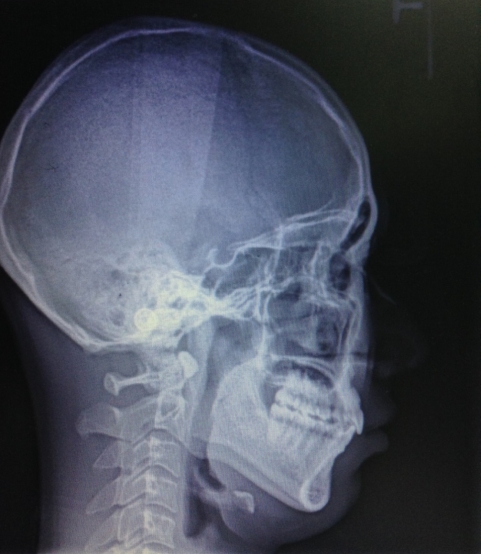

侧面观: 双唇前突 鼻唇角偏小 颏唇沟较深

X线检查 :18、28、38、48存在,下颌缺失一颗下切牙

安氏 Ⅰ类错he

骨型 Ⅰ类, 平均生长型

临床 前牙深覆合,深覆盖,后牙中性关系

上下前牙唇倾

双唇前突